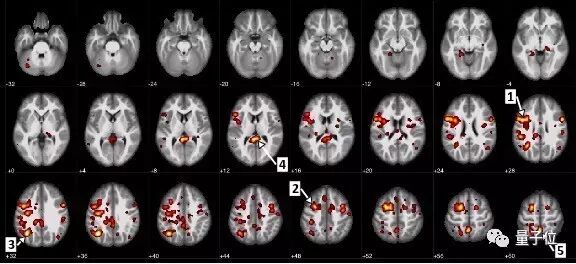

最近,IBM和阿尔伯塔大学联手进行了一项开创性的研究,使用简单的MRI(磁共振成像)扫描加一个神经网络,就能通过大脑的血流情况,来诊断神经分裂是否会发病,以及症状的严重程度。

这个研究团队,首先使用95份匿名fMRI(功能性磁共振成像)图片训练神经网络,这个数据集包括精神分裂患者和健康对照组。这些图片反映的是完成简单的音频联系后,脑内血液流动的情况。最后这个网络分辨患者和对照组的准确率达到74%。

“我们已经在大脑中发现许多异常连接,未来会进行进一步的探索研究”,阿尔伯塔大学教授Serdar Dursun说,AI创建的模型得以让研究人员更进一步。

这个模型还能预测症状的严重程度,而这可以用来制定更为有效的治疗方案。